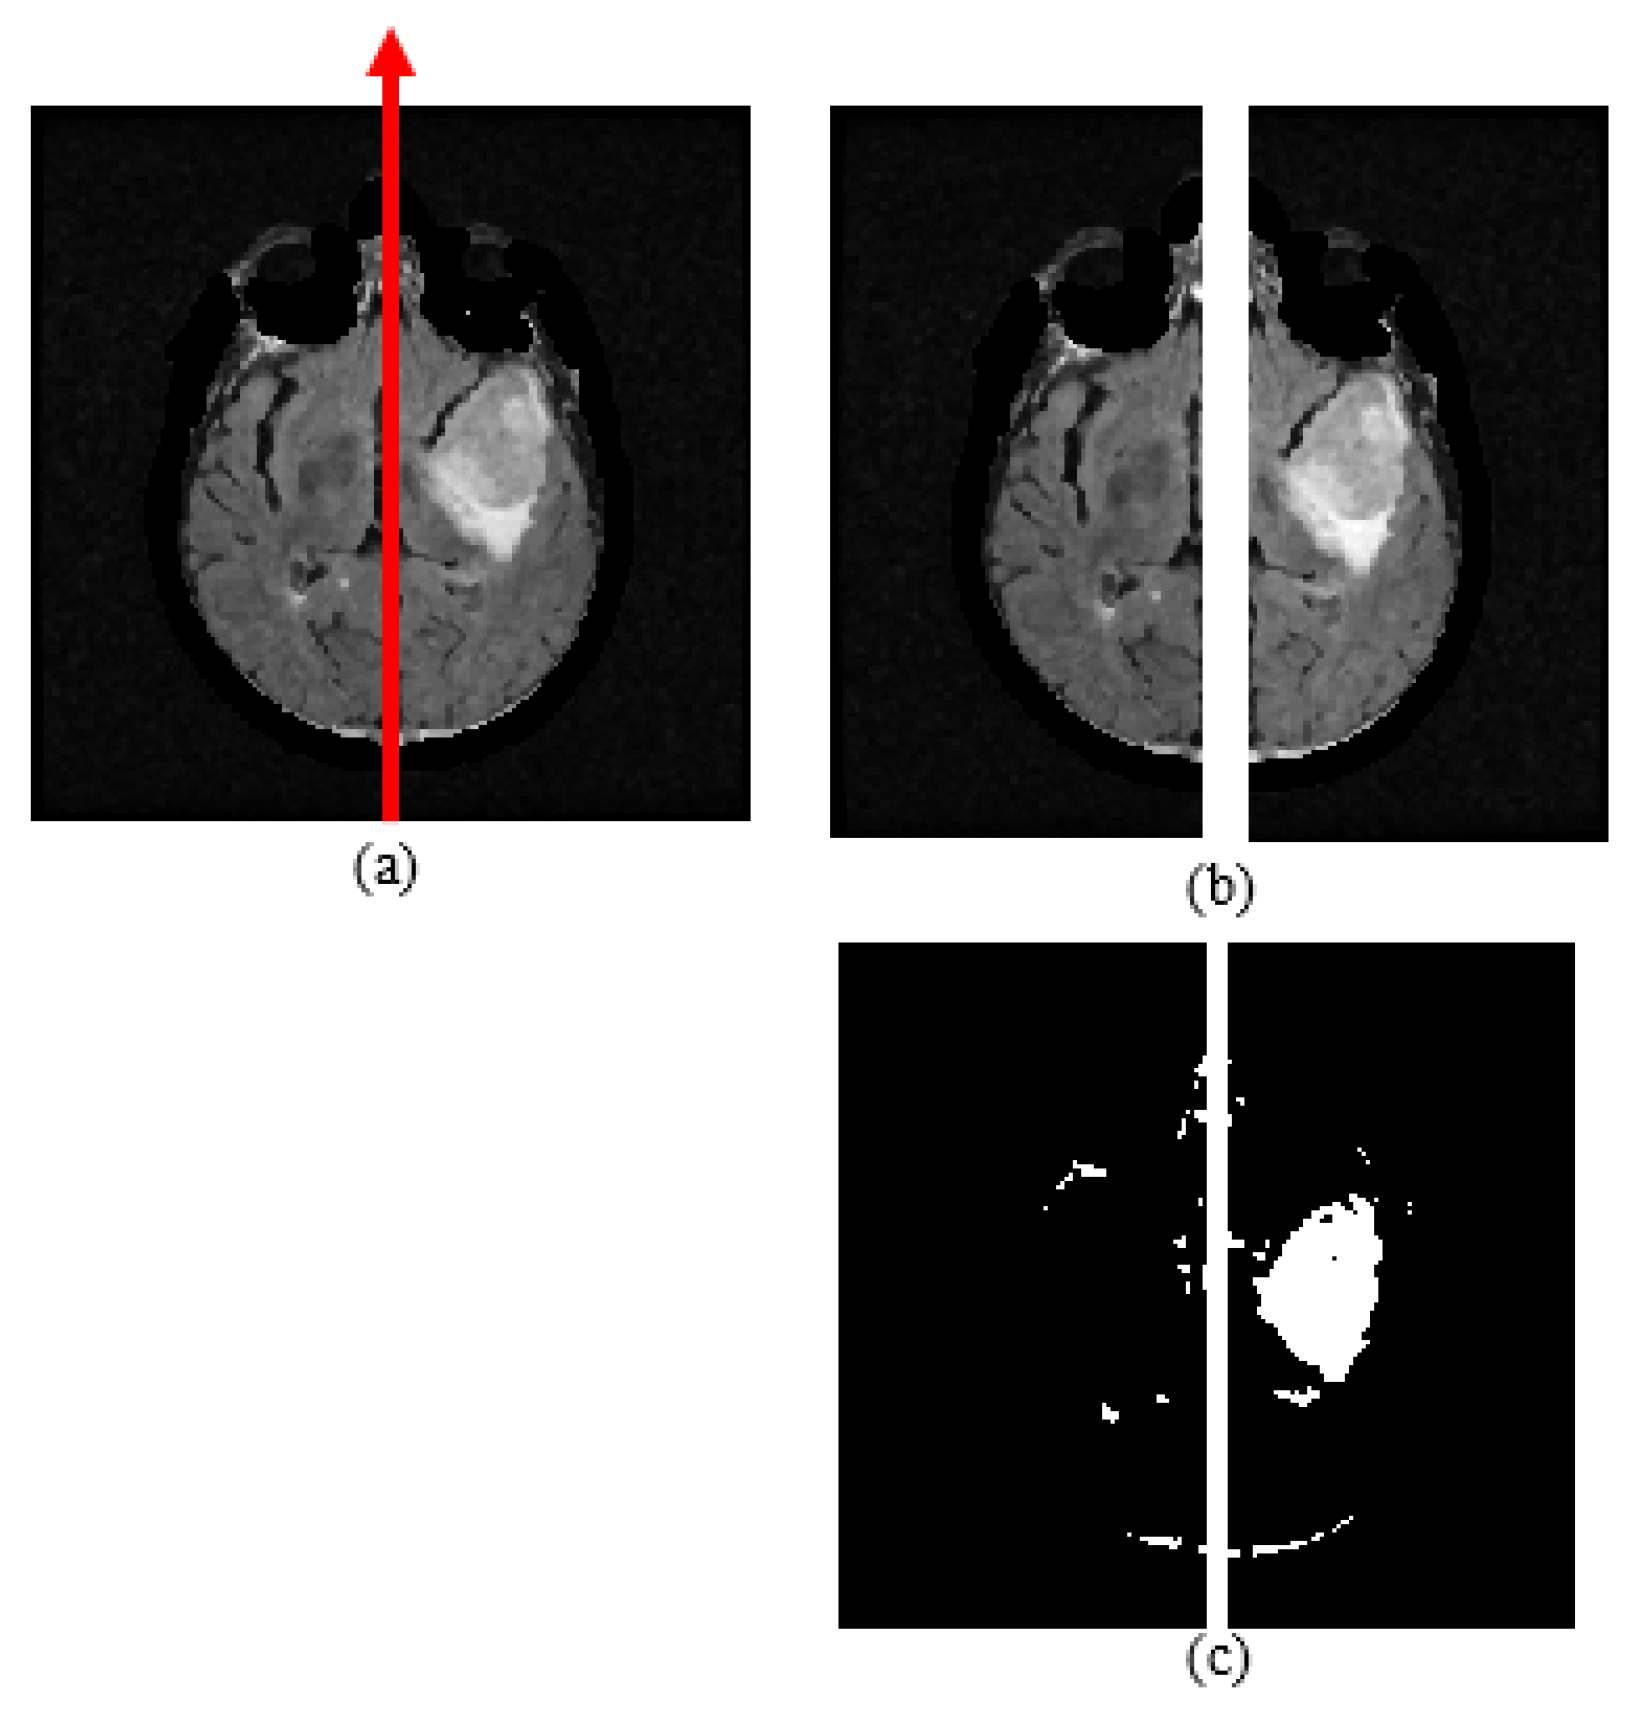

The aim of conducting the symmetry analysis is to obtain symmetry properties between the left and right brain halves. By using this analysis, a possible dissimilarity coming from a defect in a brain part, such as a tumor, can be observed between halves. Brain tumors cause edema that surrounds the abnormal region. The edema region is a high intensity level in the FLAIR modality, so the defected area in this region can be clearly observed in FLAIR images. In this study, the symmetry of two halves was examined using skull-stripped FLAIR images. A brain hemisphere including a tumor causes symmetry anomaly between the left and right parts of the FLAIR images. It is assumed that the mid-sagittal plane is a vertical line that divides the MR slice into two equal parts, so this vertical line is assigned as the geometrical symmetry axis, as shown in Figure 6a. The hemisphere containing a whole tumor is found by comparing the symmetry-based features, which are mean, area, and the Bhattacharyya coefficient (BC). While the Bhattacharyya coefficient and mean represent gray level characteristics, the area is used for examining binary characteristics of the MR image.

Figure 6.

(a) Skull-stripped FLAIR image and symmetry axis; (b) separating FLAIR image into two equal halves; (c) fuzzy c-means clustering result.

To find the area difference, the FCM clustering method is applied on the skull-stripped FLAIR image, then the binary MR slice obtained is separated into two equal halves via the vertical symmetry axis (Figure 6). Then, the left side area is subtracted from the right side area. FCM is an unsupervised clustering method, which is frequently used in medical image segmentation. Similar pixels are grouped into clusters in terms of their fuzzy memberships via fuzzy c-means clustering technique [40]. FCM is an iterative algorithm for the purpose of minimizing a cost function that is given in Equation (12). The cost function depends on the distance of the pixels to the cluster centers. In Equation (1), N, c, and represent the number of pixels, the number of clusters, and the jth pixel intensity, respectively. In this study, cluster number, c, is assigned as 3, represents the membership of the which is in the ith cluster, represents the ith cluster center, and m controls the fuzziness and it takes a constant value. Membership function and cluster centers are recalculated at every iteration by the formulas given in Equations (2) and (3) [40]: